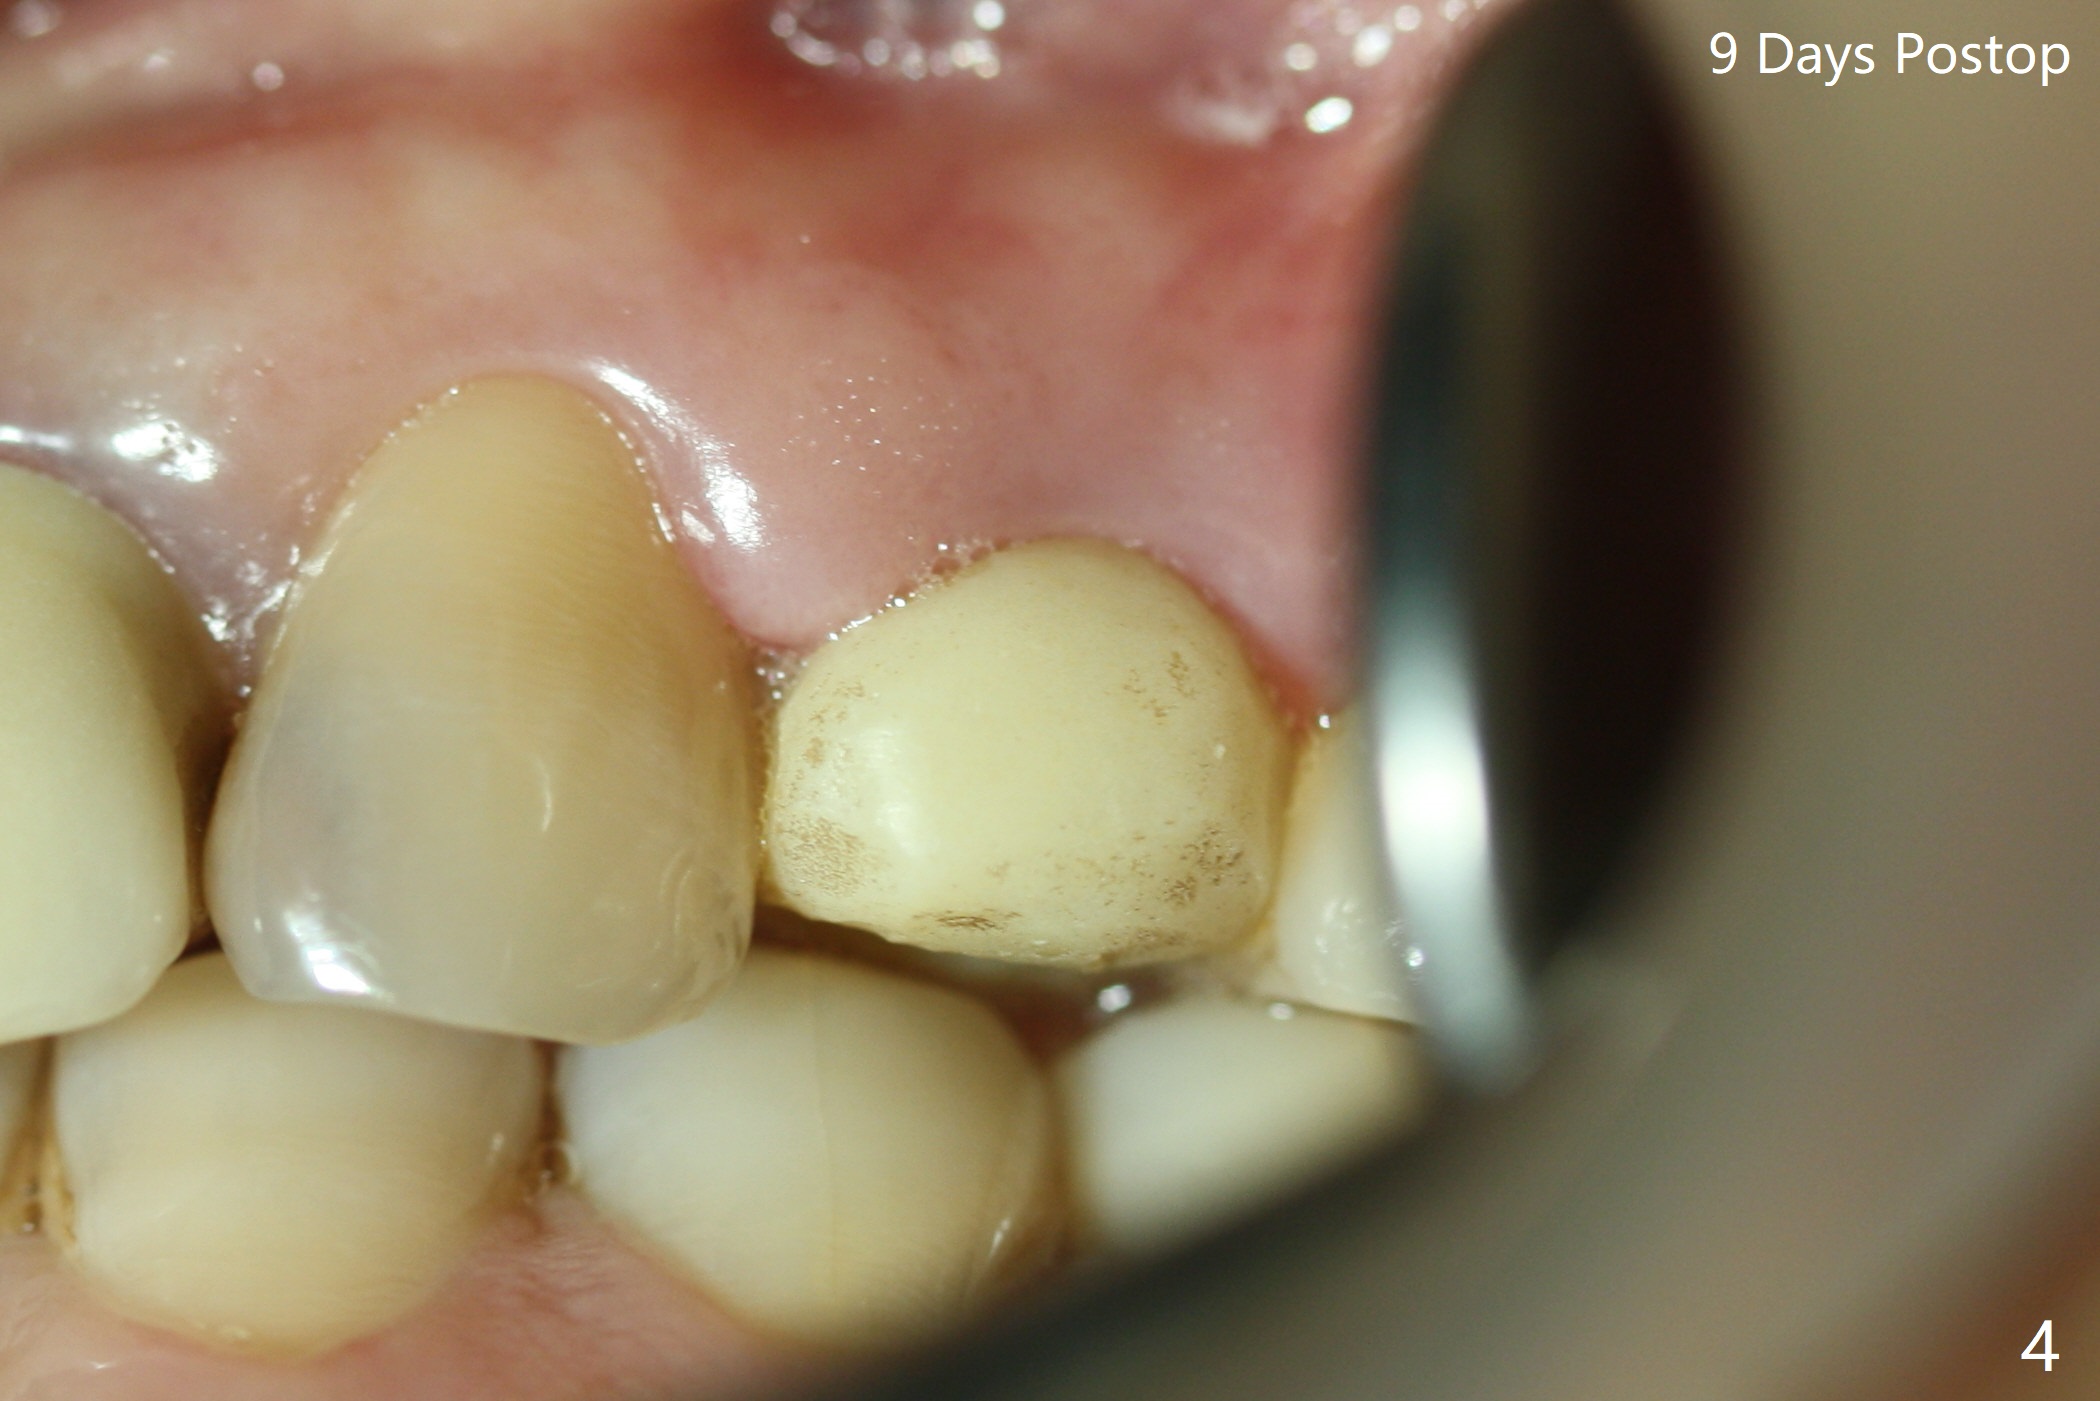

Since there is no buccal plate atrophy at 4, or 8, socket shield is not attempted at #31. Extraction turns out to be difficult because of tooth fracture. The buccal and palatal flaps have to be elevated minimally for tooth sectioning and purchase point formation. More surprising, a 4.5 mm implant appears to be too wide for the space; a 4x17 mm implant achieves insertion torque >60 Ncm (Fig.1,2). In fact Vanilla graft is placed before and after implantation. The advantage of bone graft before implant is that the graft is able to be placed as apical as possible to repair the apical defect if it is present. The disadvantage is hemorrhage. After placement of a 3.5x5 mm abutment, an immediate provisional is fabricated (Fig.3 P), which seems to be able to hold the separated buccal papillae in place. The latter heal around the immediate provisional 9 days postop (Fig.4). Because of the seal, the bone graft remains in place 1 month postop (Fig.5). There is no bone loss 5.5 months postop (Fig.6,7) or 6.5 months postop (immediately post cementation, Fig.8).